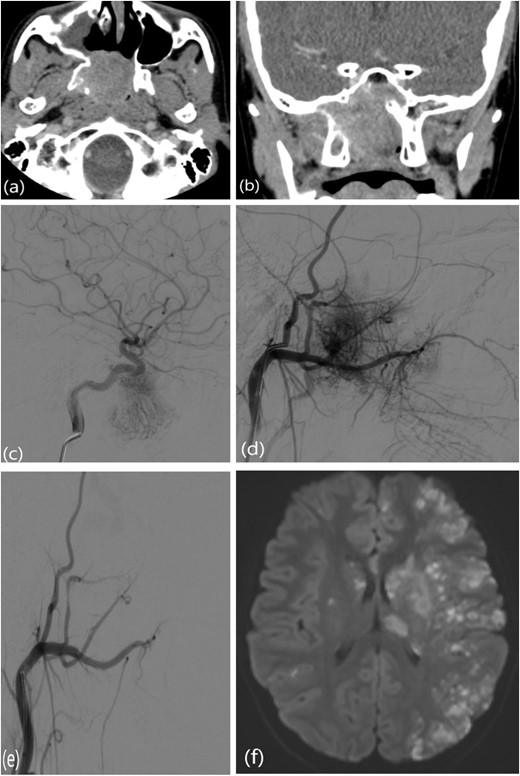

This is a case of a 12-year-old male complaining of nasal obstruction and denying epistaxis, headache, and nasal discharge symptoms. He was found to have bilateral JNA and was successfully treated with embolization of the bilateral distal IMA using polyvinyl alcohol (PVA) particles, followed by surgery. A subtotal resection of the nose, involved sinuses, pterygopalatine fossa, and infratemporal fossa was performed with no postoperative complications (Fig. 8). Six months later, the patient had a recurrence. An in-office endoscopic examination revealed a right-sided mass on the posterolateral wall, necessitating resection. One month prior to surgery, the patient was managed in the emergency department for persistent right-sided epistaxis. It lasted for eight hours and was successfully managed with tranexamic acid. CT imaging showed the recurrent right nasopharyngeal mass with skull extension into the sphenoid sinuses and the right pterygoid plate (Fig. 7a and b). Hence, he underwent embolization of the ECA (Fig. 7c–e). The patient subsequently experienced a decreased level of consciousness, aphasia, and right-sided weakness, with a power of 2/5 in both the lower and upper limbs. MRI showed multiple, extensive punctate foci of cortical and basal ganglia acute infarction complicated by edema, predominantly affecting the left side without a hemorrhagic component. Findings are consistent with showering from the PVA particles (Fig. 7f). A total of 12 months later, the patient was recovered and cleared neurologically to undergo endonasal endoscopic removal for the tumor. The patient was treated surgically at another institution, followed by a course of radiotherapy. Thereafter, he resumed his follow-up in our center, showing no evidence of recurrence after 1 year of follow-up.

(a, b) Contrast-enhanced CT of the paranasal sinuses showing a right nasopharyngeal mass with extension into the sphenoid sinuses and right pterygoid plate. (c) Lateral projection angiogram of the right ICA demonstrating the blood supply to the right nasopharyngeal mass from the inferolateral trunk. (d) Lateral projection angiogram of the right ECA showing extensive vascular supply to the hypervascular mass from multiple branches. (e) Post-embolization right ECA angiogram showing devascularization of the tumor. (f) Transaxial diffusion-weighted imaging of the brain showing extensive foci of restricted diffusion, predominantly involving the left side, consistent with acute stroke.